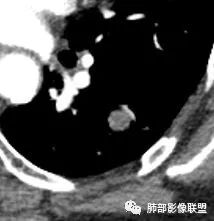

●直径约1~4cm,有完整包膜,边缘光滑或轻度分叶结节,是最常见的分叶的良性肿瘤;

●可以看到点状、块状、弧形或环形钙化灶;特征性钙化呈爆米花样,但是少见。见到钙化须与结核球鉴别。

●CT上,60%病例可见脂肪密度(CT值-40~-120HU),由于通常含有脂肪、软骨、纤维组织和上皮成分,肿块的CT值离散度大。

●强化方式取决于错构瘤的内部的成份,如果含脂肪及软骨成份较多,血管含量少,血供不丰富,CT增强仅表现为轻度强化或无明显强化;当含平滑肌及腺体成分多时,可出现较明显的强化,但少见。

●错构瘤虽然是良性肿瘤,但有时它也会缓慢生长,逐渐增大,周围血管也会出现推移,所以也会出现“血管贴边征”。